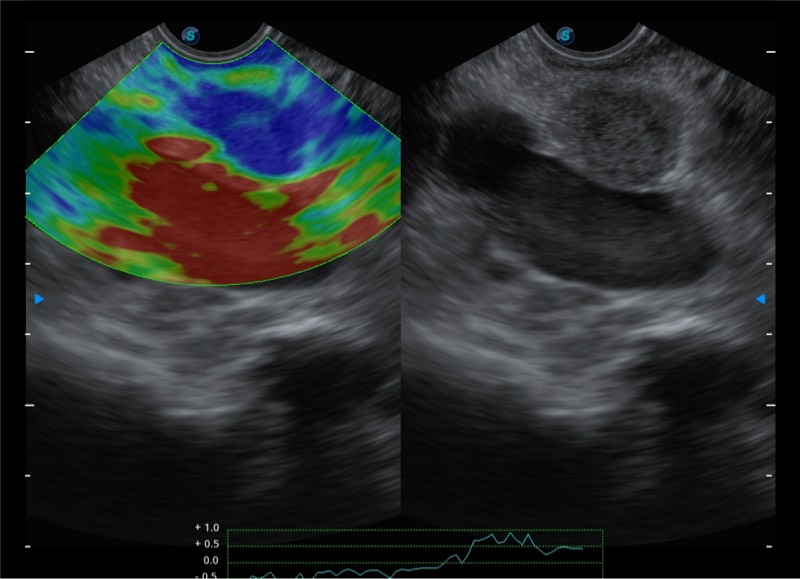

基于二十年的超声技术积累,环球UG官网提供了最新一代的独立超声主机,在提供高质量图像的同时满足多学科使用。具备常见多普勒技术并提供弹性成像、声学造影等高端影像技术。新一代传感器具有更强的抗干扰能力并减少图像伪影。

4-12MHZ宽频输出